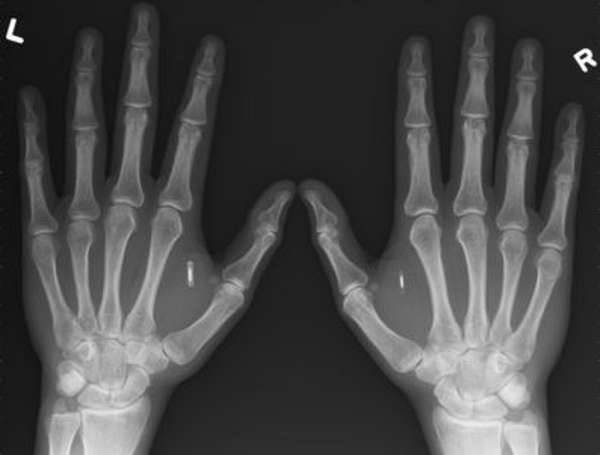

Ушиб, вывих и перелом лечатся по-разному, поэтому сначала нужно выявить причину травмы, а при необходимости сделать рентгеновский снимок.

Виды переломов

Переломы делят на две группы в зависимости от того, как расположены отломки: со смещением, без смещения. Перелом пальца со смещением может быть с расхождением или захождением отломков.

По количеству осколков выделяют: безоскольчатые, одно-, двух- и многооскольчатые. По форме линии разлома различают поперечный, винтовой, косой, Т-образный, S-образный и другие виды повреждения. По месторасположению бывают околосуставные, внутрисуставные и внесуставные или переломы диафизарной части.

Закрытый

Закрытый перелом – это внутреннее повреждение, при котором не нарушается целостность покрова кожи. Такой вид травмы менее травматичен и не угрожает заражением.

Открытый

Открытый перелом – повреждение, при котором кожный покров поврежден, часто бывает видна кость. У пострадавшего может быть кровотечение разной силы. Опасен возможностью инфицирования и серьезной травмы нервов, сосудов, связок и т.п.

Фаланги

Чаще всего, от перелома страдают отдельные фаланги пальца руки. Различают переломы:

- проксимальной фаланги,

- средней фаланги,

- дистальной фаланги (первой).

Травма основной фаланги встречается чаще остальных

Перелом ногтевой фаланги часто происходит из-за неосторожности при работе с молотком или другими инструментами. Для травмы верхней фаланги характерно массивное раздробление кости и повреждение кожи, которое может привести к инфицированию. Интересно почитать перелом кисти руки